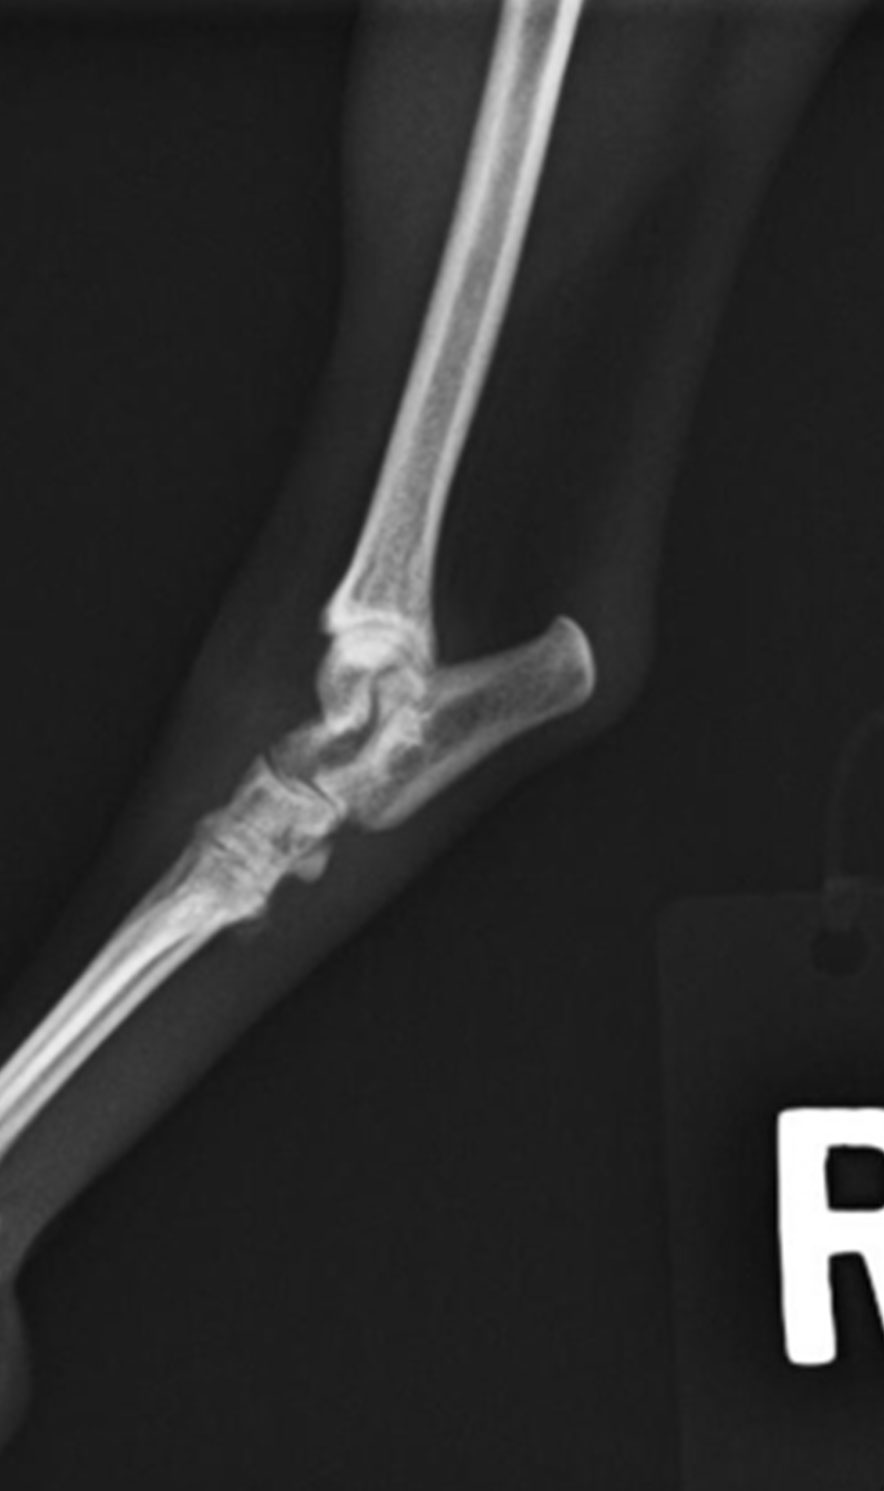

上腕二頭筋の腱や滑膜が肩の前方(右のレントゲン写真の赤矢印)あたりで損傷したり、炎症を起こす疾患です。

中型から大型の成犬や高齢犬で発症し、ラブラドール・レトリーバー、ロットワイラー、グレーハウンドが好発犬種とされています。